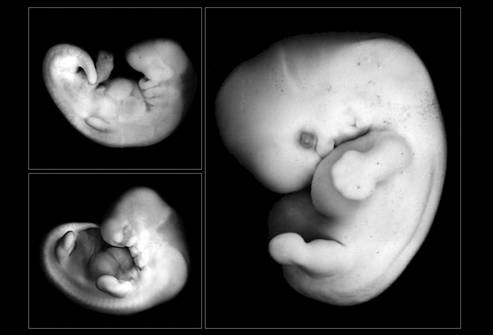

В то же время из зародышевого узелка начинает формироваться будущий человек. На этом этапе эмбрион представляет собой маленький плоский диск, состоящий из трёх слоёв, которые впоследствии будут развиваться в различные системы и органы. Его размер уже составляет 4-5 мм. К концу 4-й недели у зародыша появляется нервная пластинка – основа головного и спинного мозга. В это же время закладываются зачатки различных желез. Интересно, что уже на таком раннем сроке формируется личико с зачатками глаз.